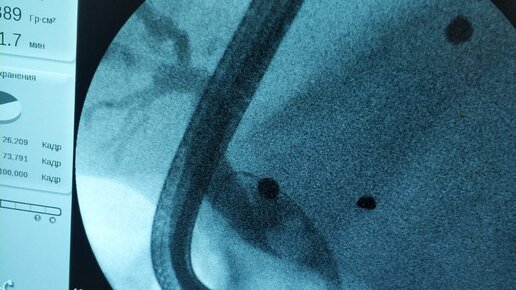

Освоен новый метод удаления камней из желчного пузыря без хирургического вмешательства

18 октября в Дагестане под руководством главного научного сотрудника научно-исследовательской лаборатории хирургической гастроэнтерологии и эндоскопии РНИМУ им. Н.И. Пирогова Станислава Александровича Будзинского прошла уникальная операция. Во время мастер-класса, посвященного эндоскопической пероральной транспапиллярной холангиоскопии, он вместе с коллегами из Республиканской клинической больницы скорой медицинской помощи (г. Махачкала) впервые в России применил новейший ультратонкий эндоскоп и электрогидравлическую литотрипсию для расщепления и удаления крупных конкрементов (камней...